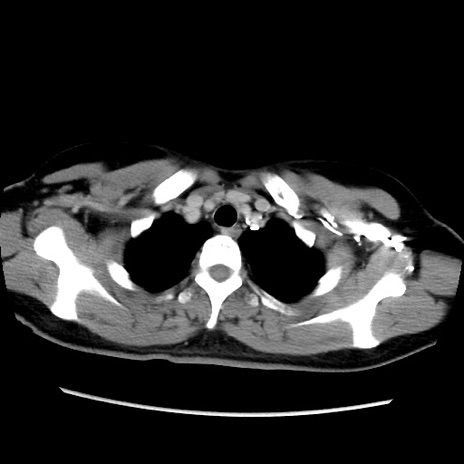

症例39(横断像)

【症例】40歳代女性

【主訴】上下腹部痛

【現病歴】2日目から下腹部痛あり。夜間は痛みで眠れなかった。昨日より上腹部痛と下痢が出現。臥位で痛みは軽快したため、休んでいた。本日になって臥位でも立位でも痛みが強くなってきたため救急要請。

【既往歴】子宮内膜症

【身体所見】部:平坦・軟、左上下腹部に圧痛あり、反跳痛あり。

【データ】WBC 21800、CRP 26.78